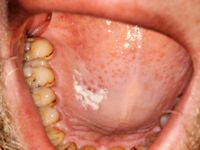

Orale leukoplakie is een witte verkleuring en verandering van het mondslijmvlies. Het komt vaak voor (bij circa 13% van de bevolking kunnen witte verkleuringen worden aangetroffen). Leukoplakie is een beschrijvende diagnose, het histologisch beeld van leukoplakie kan variëren van hyperkeratose met of zonder epitheeldysplasie, via carcinoma in situ en micro-invasief carcinoom tot invasief carcinoom. Klinisch worden er 2 varianten onderscheiden: homogene en niet-homogene leukoplakie. Homogene leukoplakie is een egaal witte verkleuring met een vlak, dun en glad oppervlak. Niet-homogene leukoplakie is een witte of witrode afwijking die irregulair vlak, nodulair of exofytisch kan zijn. Het homogene type is vaak asymptomatisch, terwijl het niet-homogene type gepaard kan gaan met pijn of hinder. Orale leukoplakie kan overgaan in een carcinoom van de mondholte; 17-35% van de carcinomen ontstaan uit preëxistente afwijkingen, vaak leukoplakie. Leukoplakie komt ook voor op andere slijmvliezen (leukoplakie van de penis of de vulva).

Leukoplakie kan worden veroorzaakt door externe factoren zoals roken, mechanische irritatie, candida. In dat geval kan het verdwijnen door die factoren weg te nemen. Indien het na 2-4 weken niet is verdwenen dan gaat het om echte leukoplakie, en is er kans op epitheeldysplasie: het advies is om een biopt af te nemen.

De mate van dysplasie wordt onderverdeeld in gering, matig en ernstig. Er is een direct verband tussen de mate van dysplasie en de kans op maligne ontaarding. De kans op maligne ontaarding binnen 5 jaar is ongeveer 5%. Het ontstaat vooral in niet-homogene leukoplakie.

Risicofactoren voor het ontstaan van leukoplakie zijn roken, alcoholgebruik, Candida infectie, HPV infectie, deficiënte voeding (vooral tekort aan vitamine A, B12, C, beta-caroteen, foliumzuur). Leukoplakie ontstaat meestal vanaf 30 jaar, de meesten zijn ouder dan 50 jaar. De kans op maligne ontaarding is verhoogd bij aanwezigheid van één van de volgende kenmerken: epitheeldysplasie in het biopt; niet-homogene type; vrouwelijk geslacht; langer bestaande leukoplakie; leukoplakie bij niet-rokend persoon; locatie in de mondbodem of op de tong; aanwezigheid van C. albicans.